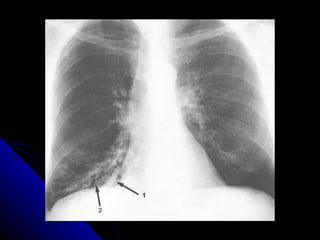

BBrroonncchhiieeccttaassiiss

RRiinngg sshhaaddoowwss,, aanndd hhoonneeyy ccoommbb..

TTrraammlliinnee sshhaaddoowwss..

TTuubbuullaarr sshhaaddoowwss..

GGlloovveedd ffiinnggeerr sshhaaddoowwss..